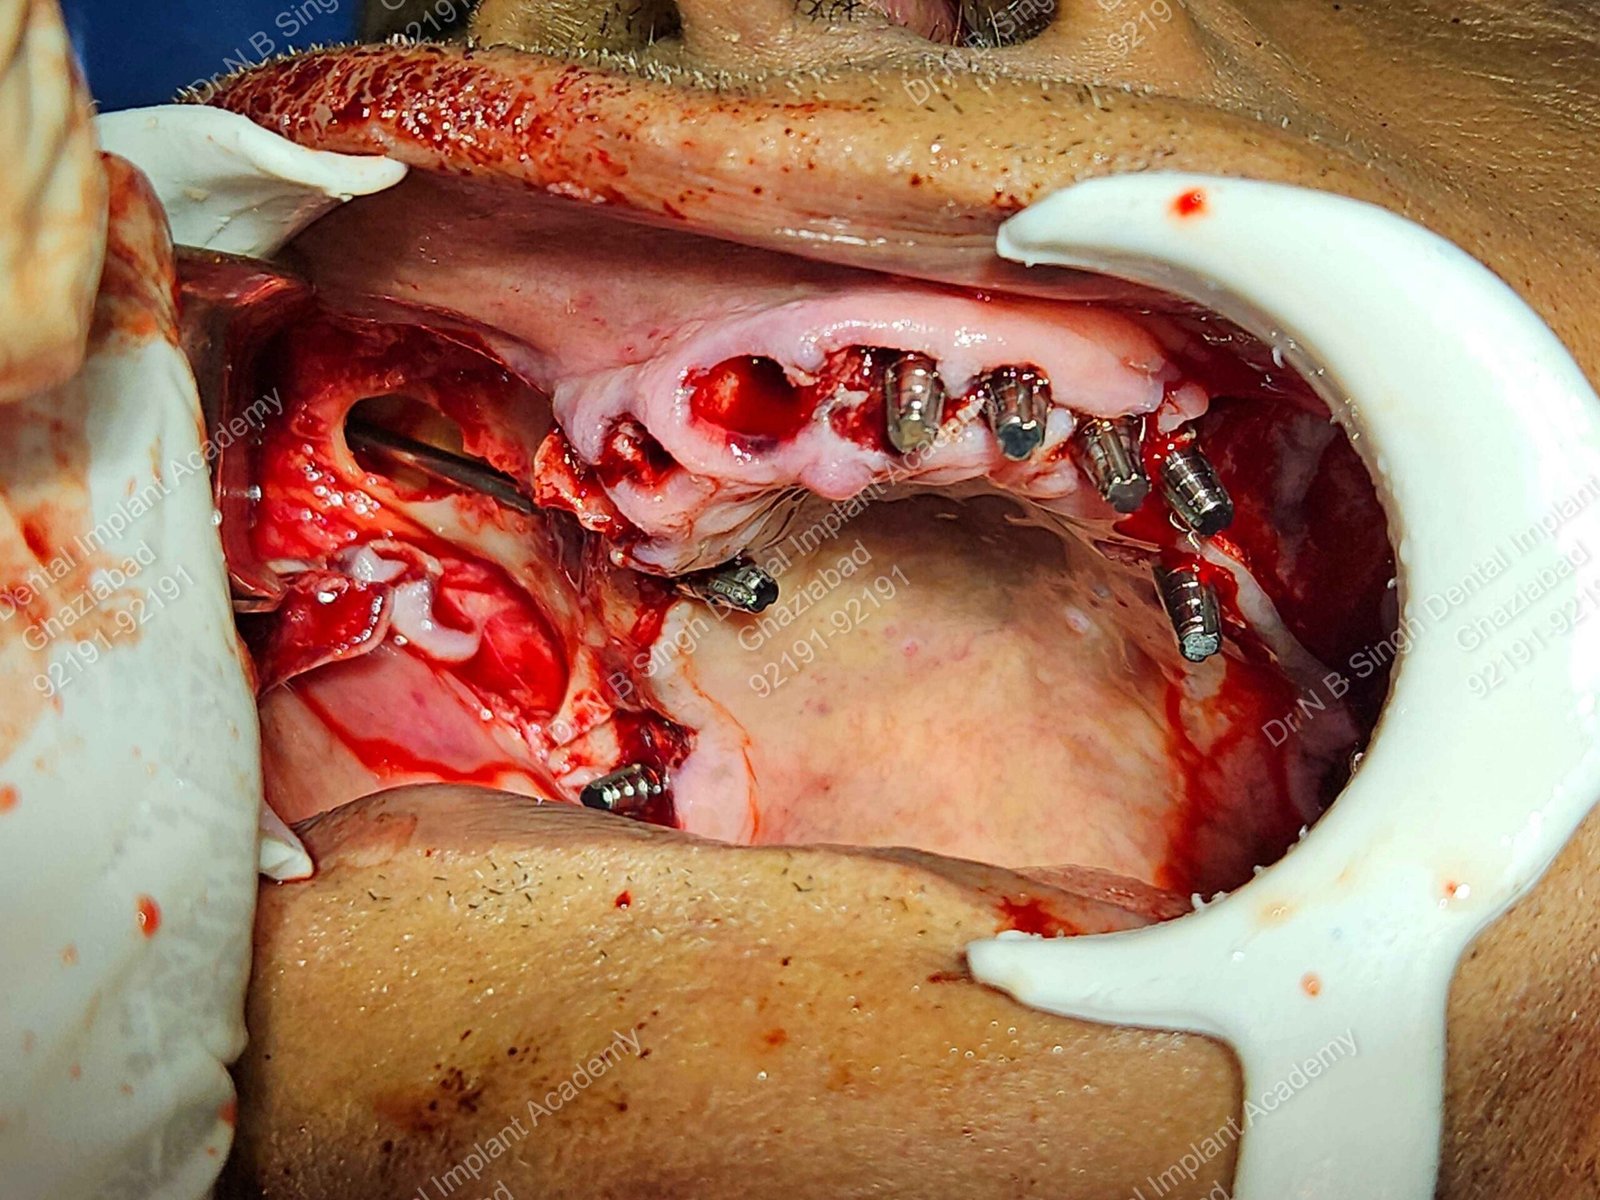

1005 zygomatic basal implant full mouth Ali Hasan 2

C1005 zygomatic basal implant full mouth – Ali Hasan 4